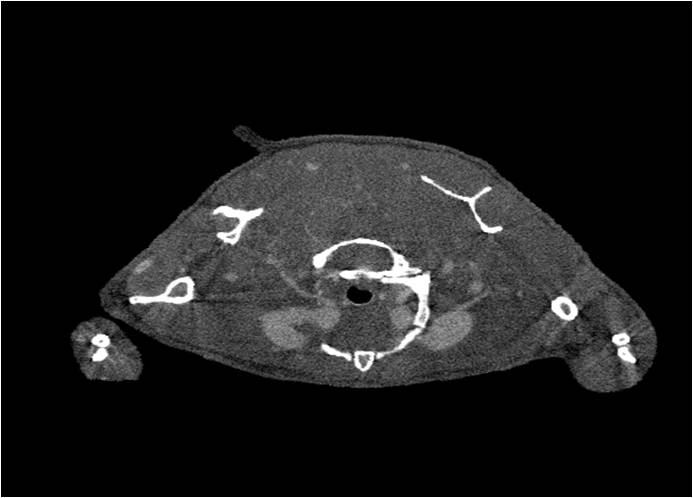

小鼠模式,22.5μm像素

正常

肺轉移

8天 14天

無(wú)造影劑注入 造影劑注入